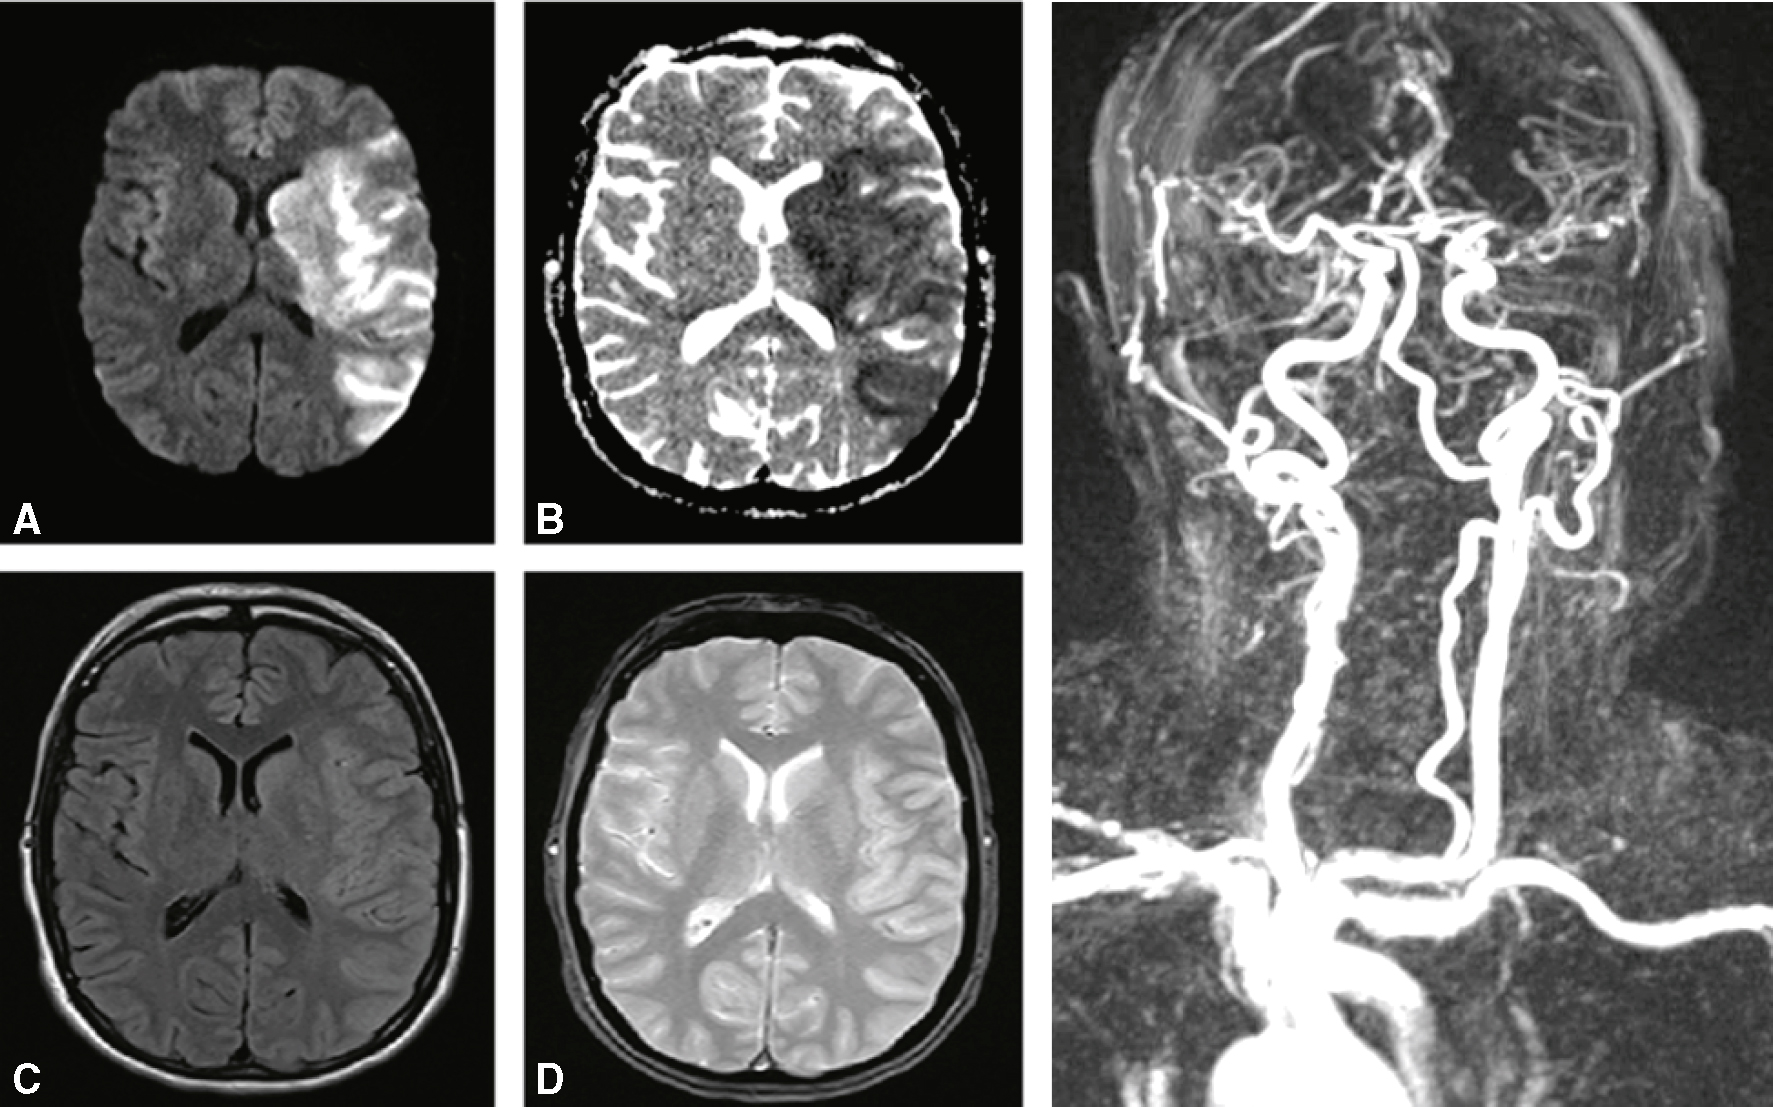

Quelles sont la (les) proposition(s) exacte(s) concernant cette IRM cérébrale (fig. 32.10) ?

L'assemblage affiche cinq photographies de la coupe axiale du cerveau (A à D) et de l'angiographie par résonance magnétique (à droite) montrant des coups ischémiques dans l'hémisphère gauche. En diffusion, cette photo montre le ventricule frontal du cortex cortitique sur le côté gauche, qui est caractéristique de l'infarctus aigu. L’image B en cartographie ADC révèle une hypointensité concordante avec la restriction de diffusion, confirmant l’ischémie récente. L’image C en séquence FLAIR illustre un hypersignal modéré dans la même région, avec un discret effacement des sillons corticaux. L’image D en T2 montre une hyperintensité similaire, sans effet de masse ni saignement apparent. L’angiographie à droite met en évidence une occlusion ou une réduction de calibre de l’artère cérébrale moyenne gauche, avec un contraste net des vaisseaux du polygone de Willis. L’ensemble est compatible avec un AVC ischémique étendu du territoire de la cérébrale moyenne gauche.